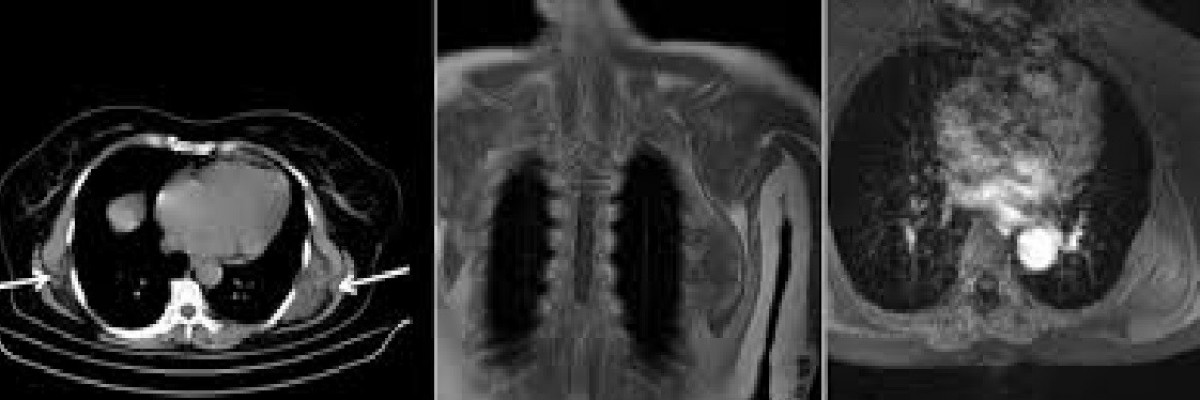

Sırt nasırlarının 5 santimden büyük oldukları zaman belirti vermeye başladıklarını ifade eden Prof. Dr. Özkan Demirhan,” Olguların yüzde 50’si genelde belirti vermez. Belirti veren durumlarda hastaların çoğunda sırtta kürek kemiği etrafında şişlik, kolda kuvvetsizlik, sırt omuz ağrısı görülmektedir. Diğer belirtiler arasında kol hareketiyle ortaya çıkan kürek kemiğinin kitleye takılmasına bağlı tıkırtı sesi (click), eklem sertliği, kürek kemiğinin diğer tarafa göre yüksek olması gibi yakınmalar sayılabilir. Bu yakınmalarla başvuran hastalar, fizik muayenede anormal bulgu yok ise de mutlaka radyolojik olarak değerlendirilmelidir. En basitinden komplekse doğru Ultrasonografi (USG), Bilgisayarlı Tomografi (BT) ve MRG inceleme bu patoloji için oldukça yararlı görüntüleme yöntemleridir. Radyolojide bazen toraks duvarı kasları ile net ayırt edilemeyen, malign kitle benzeri lezyon olarak tanımlanır. Aslında Elastofibroma Dorsi açısından lezyonun yeri ve kliniği tipiktir radyolojik olarak da tipik bulgular elde edildiği için insizyonel biyopsiye gerek yoktur. Elastofibroma Dorsi tanısında görüntülemenin yeterli olmadığında ve agresif bir tümör gibi düşünüldüğü zaman nadir de olsa biyopsi yapılması gerekebilir. Fakat derin yerleşimli yumuşak doku ve yağ dokusuna uzanan karakteristik lezyonlarda başka testlere gerek olmayabilir. Küçük Elastofibroma Dorsi olgularında BT ve MR yeterli olmayabilir. O zaman gadolinium kullanılabilir. Bilgisayarlı tomografinin Elastofibroma Dorsi tanısındaki duyarlılığı MRG'ye göre daha düşüktür. Ancak tipik lokalizasyonu ve iki taraflı lezyon olması durumunda BT tanıda yardımcı olabilir. MRG bulguları varlığında elastofibroma dorsi tanısı kolaylıkla düşünülebilir. MRG'de atipik bulguların varlığı durumunda ise lezyonun tipik lokalizasyonu, iki taraflı (bilateral) oluşu, hastanın ileri yaşta ve kadın hasta olması elastofibroma dorsi tanısını destekler. Lezyonun iki taraflı olması ayırıcı tanıda düşünülebilecek malign kitleleri büyük oranda ekarte edebilir. Bu yüzden elastofibroma dorsi tanısından klinik olarak şüphe edildiğinde göğüs duvarı mutlaka iki taraflı değerlendirilmelidir. Ayırıcı tanıda diğer göğüs duvarı tümörleri de akla gelmelidir.” şeklinde bilgi verdi.